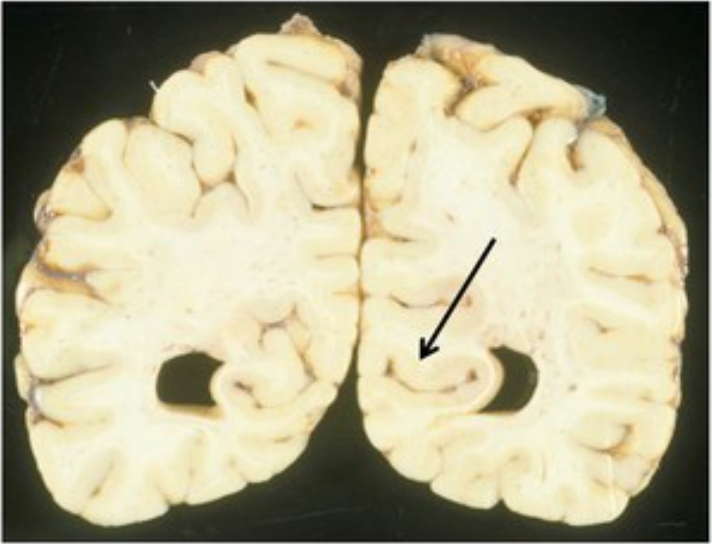

Identify

calcarine sulcus

What artery is responsible for this infarct?

Anterior cerebral